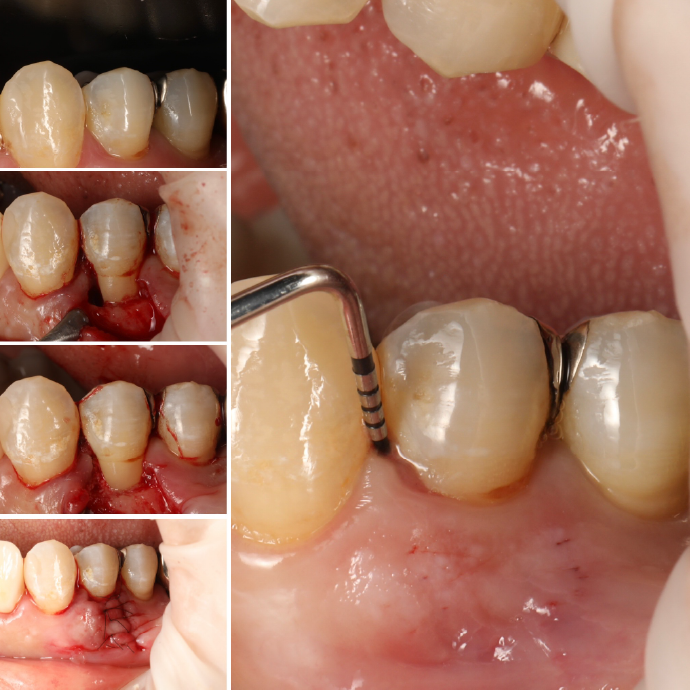

SRPでも改善が見られない重度の症例では、歯肉を切開してポケット奥深くまで歯石などを除去する外科的処置を行います。

歯周病によって破壊された歯周組織(歯肉・歯槽骨など)を、骨補填材や薬剤を用いて再生を促す治療です。適応症例・術後管理が重要です。

| 治療内容 | 上段 根面被服術(歯茎を上げる手術) |

| 治療費 | 総額 88000円〜 |

| 治療回数 | 1回 |

| リスク | 術部の発赤、腫脹、疼痛、部分的なネクローシス |

| 治療内容 | 下段 歯周外科(再生療法) |